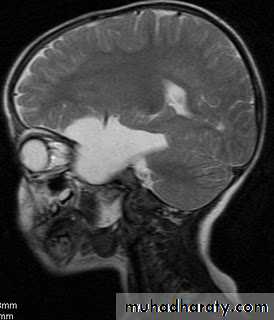

Chiari malformation:

Called also Arnold-Chiari Malformations:

Herniation of posterior fossa contents (e.g. cerebellar tonsils) through the foramen magnum.

Normally up to 5mm of tonsillar descent through the foramen magnum.

Chiari I: >5 mm of tonsillar descent.

Chiari II: descent of the tonsils and cerebellar vermis.

Chiari malformation Type II

Developmental Abnormalities of the Nervous System

Presentations:

Chiari I Malformation present in young adults with headache, exacerbated by coughing and straining.

Chiari II malformation present in infancy with signs of brainstem compression such as poor feeding, stridor and apnoeic spells.

Treatment of Chiari malformation include:

• Treatment of associated Hydrocephalus, and then

• Foramen magnum decompression.